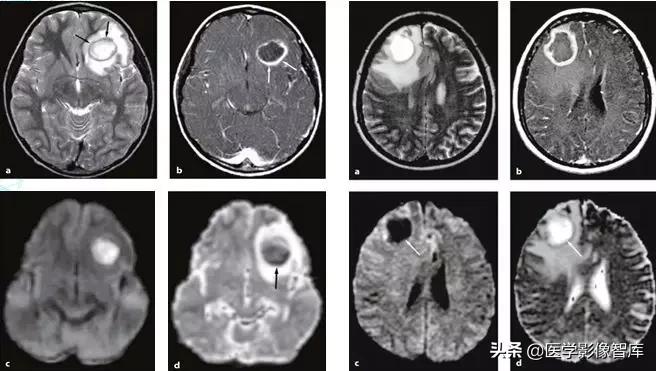

脑肿瘤

脑肿瘤的DWI信号主要取决于ADC值(细胞密度)与T2信号。低ADC值反应了高细胞密度和减少的细胞外间隙;高ADC值反应了低细胞密度,低细胞核浆比,细胞外基质增多(如图9)。高级别胶质瘤(包括间变性胶质瘤、间变性少突胶质细胞瘤、胶质母细胞瘤等)、淋巴瘤、转移瘤、髓母细胞瘤、中枢神经细胞瘤、原始神经外胚层肿瘤PNET等脑肿瘤,通常表现为DWI高信号、低ADC值。

相对ADC值:淋巴瘤<高级别胶质瘤<转移瘤。

对于胶质瘤而言,低级别的胶质瘤细胞密度稍低,其DWI呈等或稍高信号,高级别的胶质瘤则细胞密度较高,其DWI呈高信号,ADC值降低。这不是绝对的,因为DWI高信号还包含了T2信号,因此,有些肿瘤DWI高信号部分同时包含ADC低信号(弥散受限的部分)和等/高信号(T2投射效应的部分)。